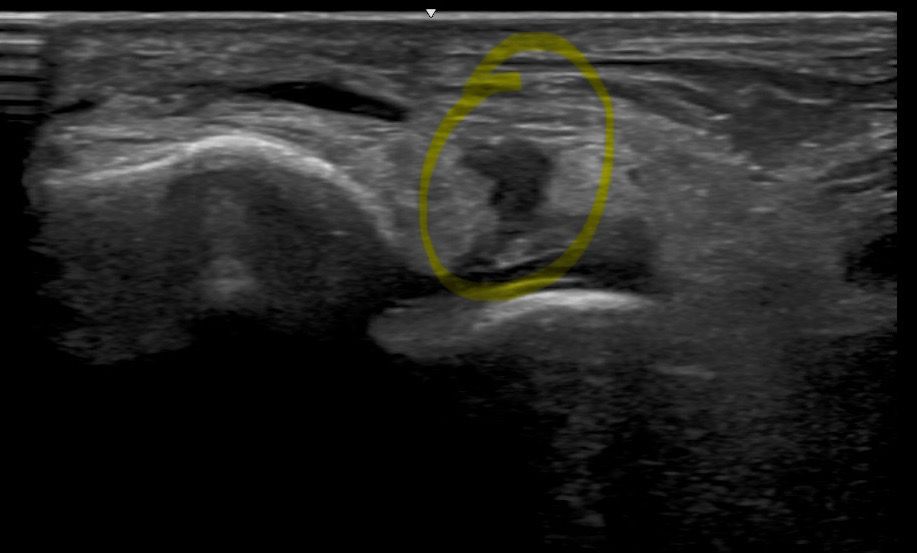

사진은 다친지 일주일차에 내원했을때 전거비인대 초음파사진입니다.

병원은 두곳 가봤고 두곳 모두 전거비인대 완전파열 진단받았습니다. 한곳은 수술소견, 한곳은 수술이나 보존적치료 선택하라는 소견 받았습니다.

이번주가 2주차인데, 어제 초음파에서는 저 사진보다 간격은 많이 좁아졌는데 전혀 안붙었다고 했습니다.

일단 현재 초음파상으로도 인대의 완전 파열로 보여집니다.

사진상의 간격이 좁아졌지만 붙지 않았다는 소견으로 보아, 인대파열 이후 회복과정에서 연결조직의 형성이 관찰되지 않은 것으로 볼 수 있습니다.

경과는 조금 더 지켜보시는 것도 좋겠지만, 이번에 올려주신 사진과 같이 큰 차도가 앖다면 수술적인 치료가 필요할 수 있는데요, 전거비인대는 발목의 안정성을 제공하는 역할을 하기 때문에,

사진상 전거비인대가 불연속적으로 보이고 그 사이에 저에코 영역이 확인돼 완전파열 소견과 일치합니다. 2주차에 간격이 좁아졌으나 유합 없이 유지중이라면 비수술 재활 시 충분한 고정 및 장기 재활이 필요합니다. 고강도 스포츠 복귀를 원한다면 수술 후 재활이 재파열 불안정성 감소 측면에서 유리할 수 있어 마지막 병원의견 꼭 참고하세요!